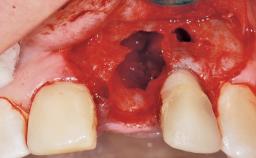

Late Flapless Placement of an Implant in a Maxillary Left Central Incisor Site

A 39-year-old male patient presented with a chief complaint of discomfort and gingival discoloration around his maxillary left central incisor. He was in good general health and was a non-smoker. His past dental history was significant because of the traumatic fracture of tooth 21 in a sporting accident at age 13. Initial dental treatment included endodontic therapy and a full-coverage restoration. The patient became symptomatic 5 years later, when structural failure of the tooth resulted in the dislodgment of the crown. Endodontic retreatment, apical surgery, and post-and-core restoration were performed.

| Bone Volume | Deficient horizontally, requiring prior grafting |